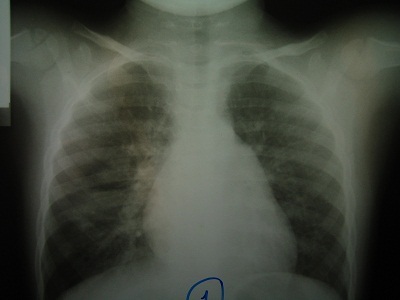

Em V. 4 tuổi ở Hóc Môn, đến khám bệnh vì ho, khò khè, thở mệt từ 5 hôm nay. Bác sỹ khám thấy lồng ngực của em có nhiều ran rít và ran ngáy và được chẩn đoán là hen suyễn bội nhiễm. Bác sỹ cho em dùng thuốc corticoid đường uống kết hợp kháng sinh và thuốc dãn phế quản phun mù. Triệu chứng ho của em có giảm nhưng cứ dai dẳng mãi. Người nhà đưa em V. đến khám theo chương trình Hội chẩn chuyên môn bệnh hô hấp khó trị tại trung tâm điều trị bệnh hô hấp Phổi Việt. Tại đây, em được cho chụp phim X quang phổi phát hiện thấy hạch rốn phổi trái và xẹp thùy phổi trên bên trái. Chụp phim CT scan cho thấy rõ hình ảnh hạch lao bên trái chèn ép phế quản thùy lưỡi gây xẹp hẳn thùy lưỡi. Điều trị kháng lao được tiến hành và em V. giảm triệu chứng ho sau 2 tuần.